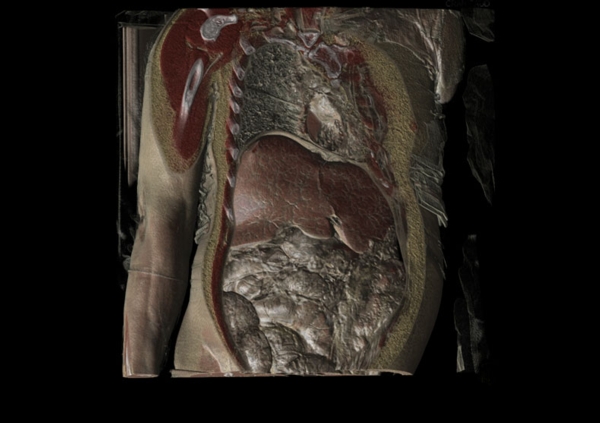

在随后的幻灯片中,您将看到来自瑞典医学图像科学与可视化中心(the Center for Medical ImageScience and Visualization ,CMIV)的Anders Persson和他的同事们运用CT,MRI和超声得到的令人惊叹的尸检图片。这些图片描绘了人体骨骼,消化道,循环系统和大脑以及野猪的前端结构。

3, 人体,正俯视;皮肤,皮下脂肪和多个器官清晰可见。